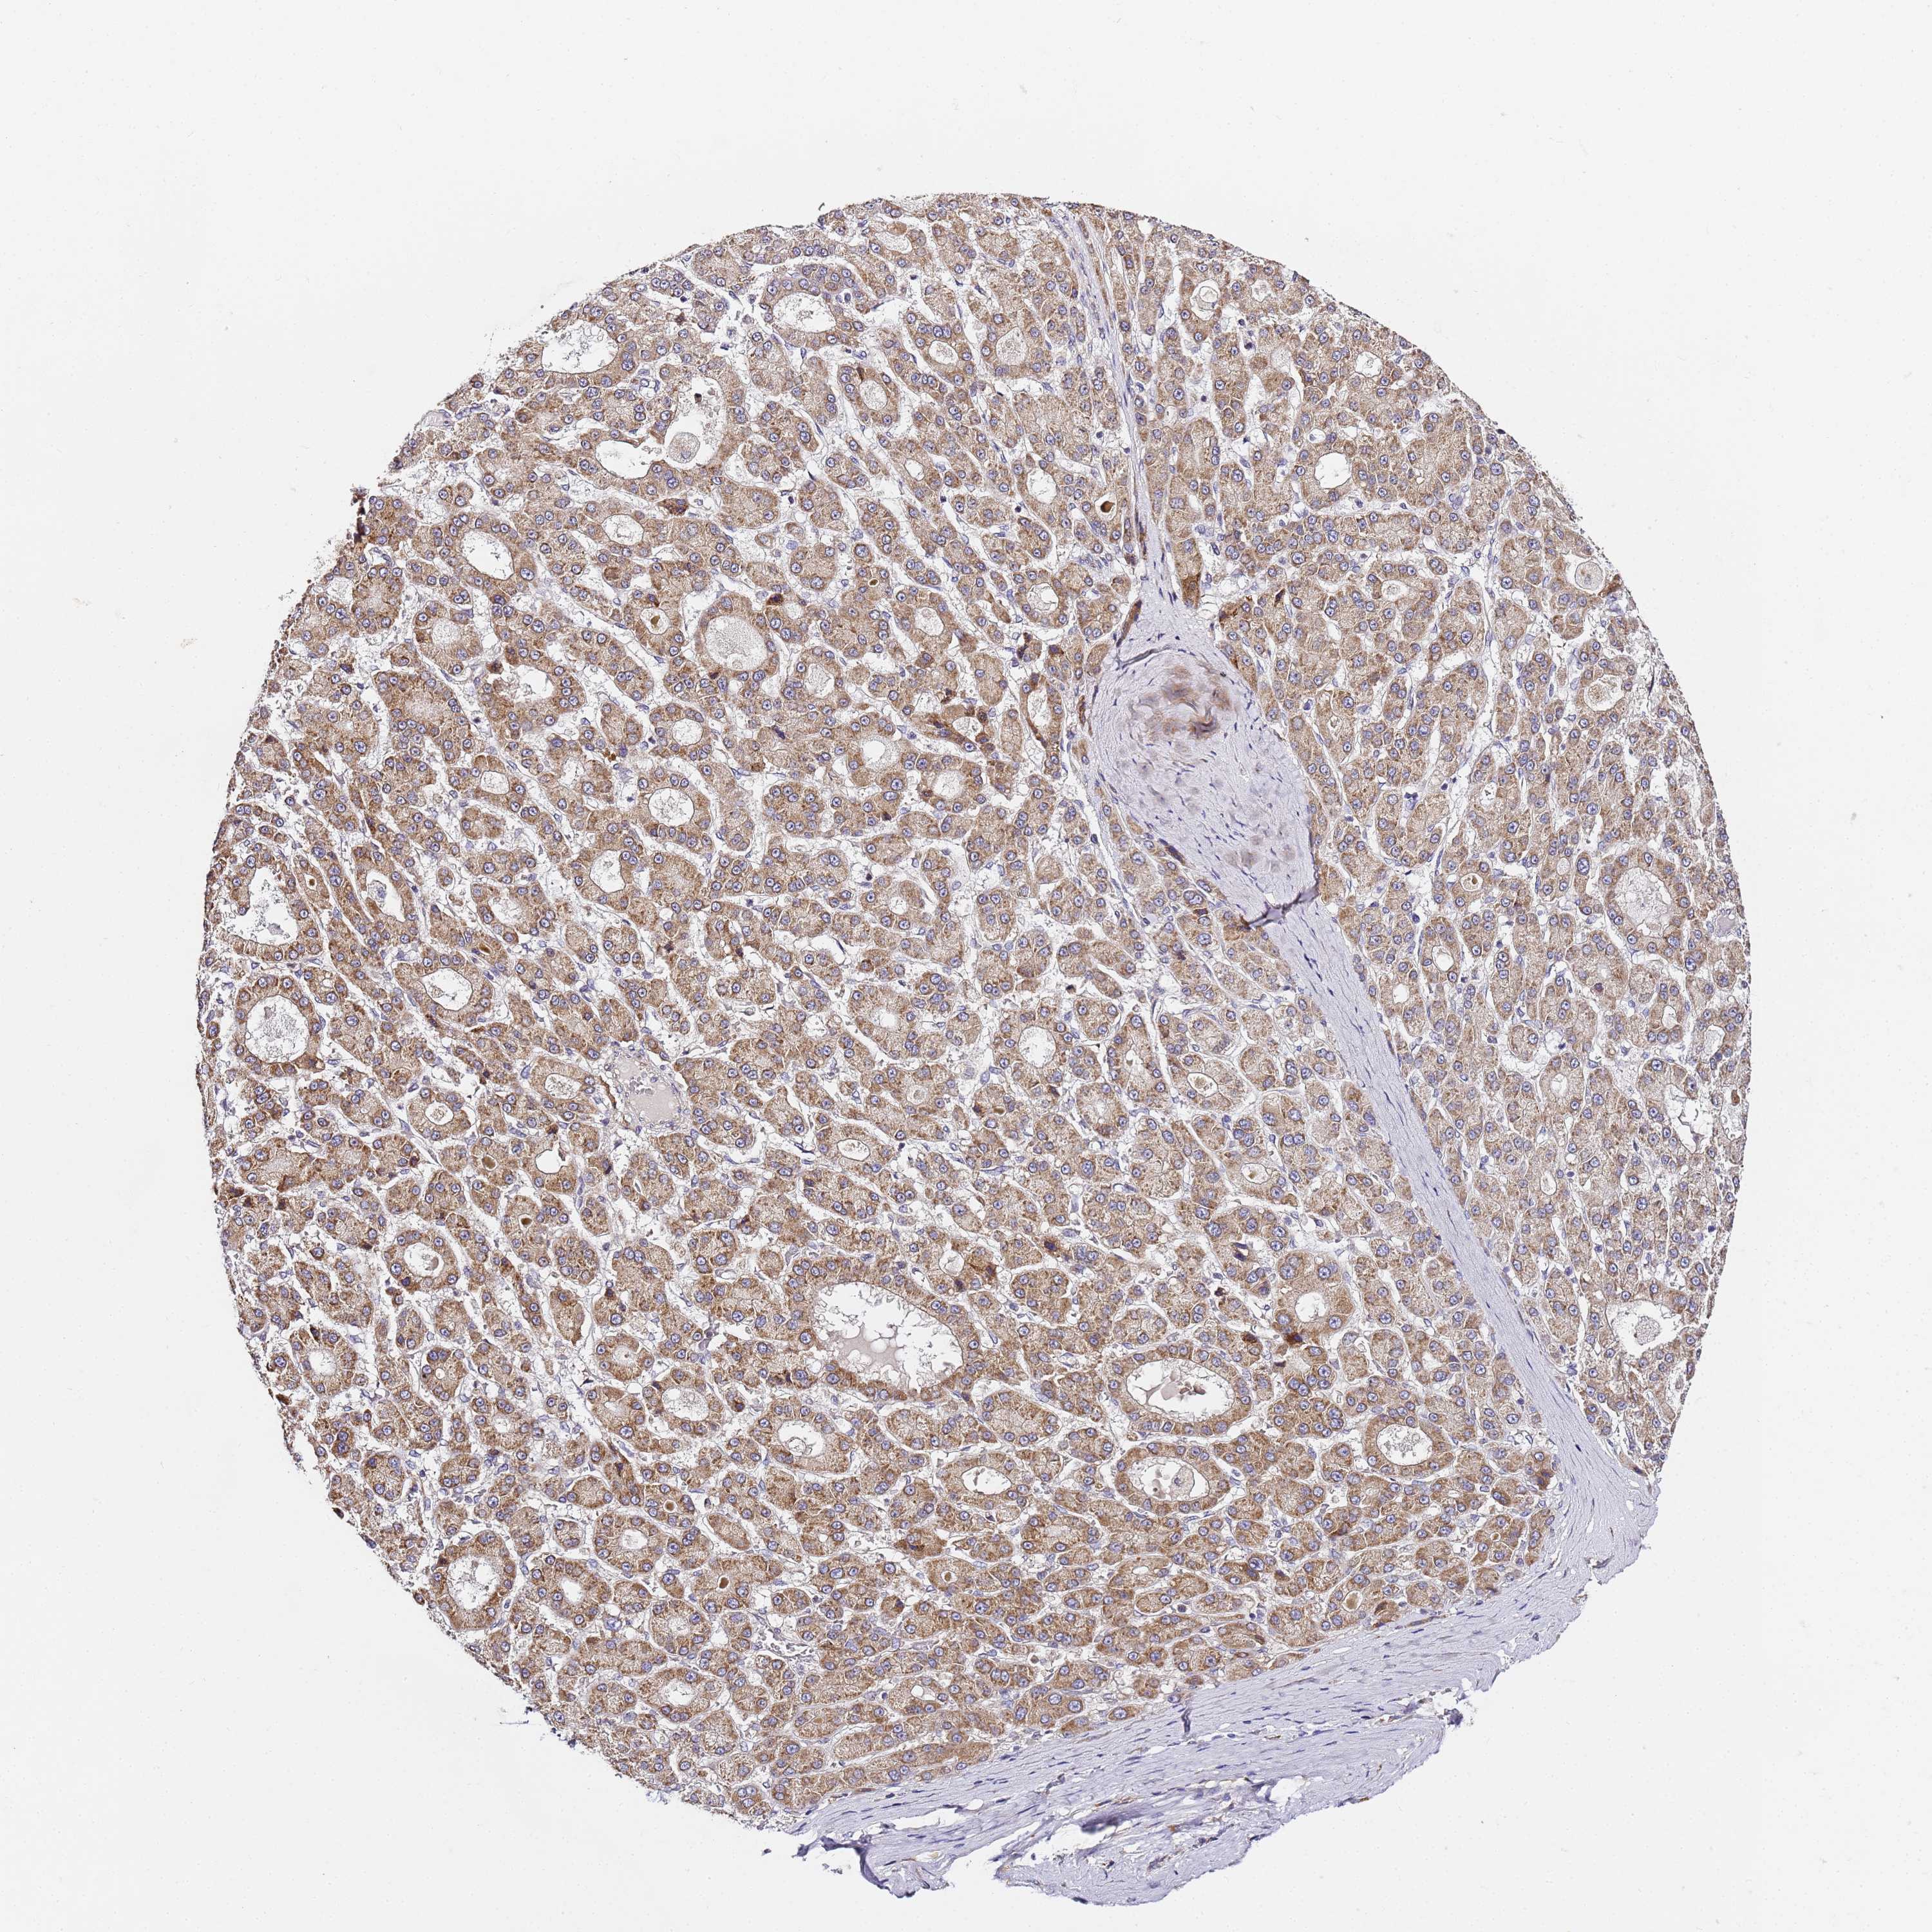

LIVER CANCER - Protein expressioni

A mouse-over function shows sample information and annotation data. Click on an image to view it in a full screen mode. Samples can be filtered based on level of antibody staining by selecting one or several of the following categories: high, medium, low and not detected. The assay and annotation is described here.

Note that samples used for immunohistochemistry by the Human Protein Atlas do not correspond to samples in the TCGA dataset.

Antibody stainingi

Antibody staining in the annotated cell types in the current human tissue is reported as not detected, low, medium, or high, based on conventional immunohistochemistry profiling in selected tissues. This score is based on the combination of the staining intensity and fraction of stained cells.

Each image is clickable and will lead to virtual microscopy that enables deeper exploration of all samples and also displays staining intensity scores, fraction scores and subcellular localization as well as patient and tissue information for each sample.

Antibody HPA038751

Staining

High

Medium

Low

Not detected

Intensity

Strong

Moderate

Weak

Negative

Quantity

>75%

75%-25%

<25%

None

Location

Nuclear

Cytoplasmic/membranous

Cytoplasmic/membranous,nuclear

Cholangiocarcinoma

Carcinoma, Hepatocellular, NOS